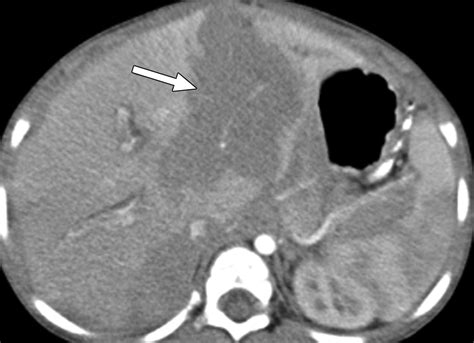

Imaging Scans (CT, PET, MRI) Creating detailed pictures to determine the location and size of tumors.

Bone Marrow Aspiration Checking if cancer cells have spread to the bone marrow.